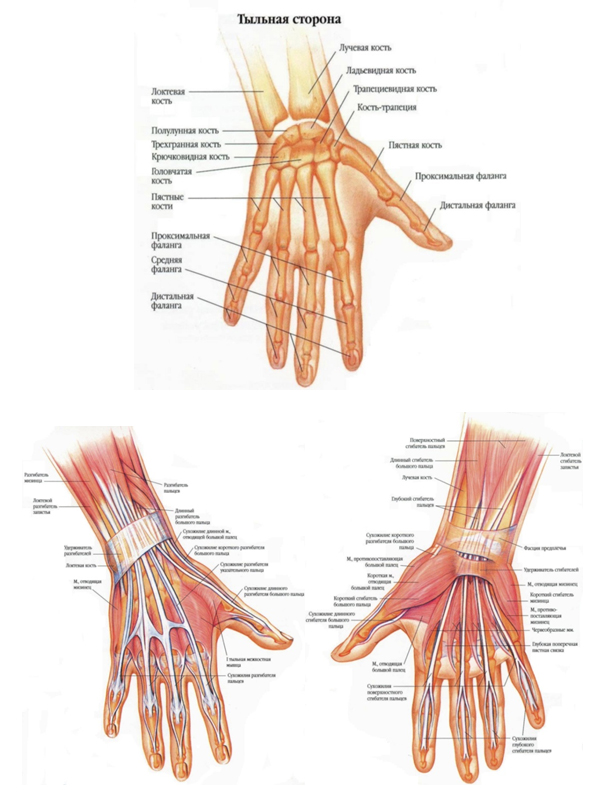

Анатомия кисти руки и строение костей